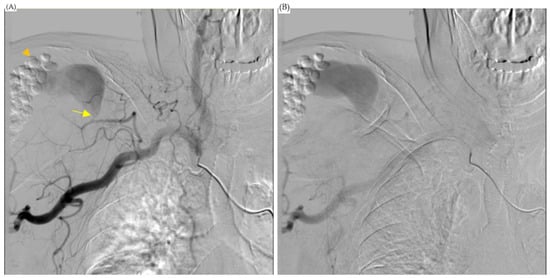

Figure 3.

Angiogram showed a pseudoaneurysm. (A) Angiogram showed that the feeding artery of the pseudoaneurysm was the thoracoacromial artery, acromial branch (arrow). Antibiotic beads were noted in this angiogram (arrowhead). (B) The aneurysm extended to acromion of scapula.

The cardiovascular department was consulted for further treatment, and an angiogram of the right shoulder was arranged. It revealed a pseudoaneurysm fed by the acromial branch of the thoracoacromial artery (Figure 3). An operation to embolize the pseudoaneurysm proceeded with the patient in a supine position with her right arm stretched out. A minimal incision was made in the brachial artery above the elbow and a 10 cm, 6 Fr. endovascular therapy sheath (TERUMO CORPORATION, Radifocus Introducer II M, Tokyo, Japan) was inserted. Endovascular surgery was performed on the thoracoacromial feeder artery with a 0.89 mm (in diameter) × 220 cm (in length) Terumo guidewire (TERUMO CORPORATION, Radifocus guidewire M, Tokyo, Japan) and a 100 cm JB1 sheath (Cook Medical, JB1 sheath, Bloomington, IN, USA). Three embolization tornado coils (Cook Medical, Tornado Embolization Coil, Bloomington, IN, USA) were used to embolize the feeding vessel, and at the end of the surgery, an intra-operation angiogram showed complete occlusion with no contrast enhancement in the pseudoaneurysm (Figure 4).